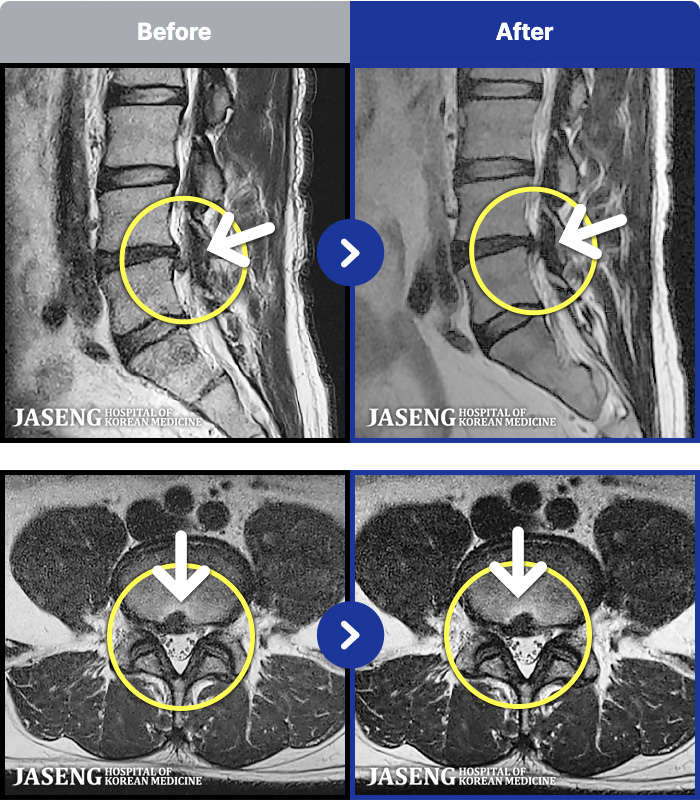

1,291 MRI ũ ʸ Ȯϼ.

[뱸] 19.11.28~25.05.06